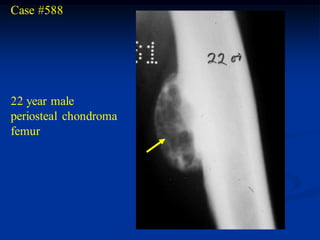

Case #588

22 year male

periosteal chondroma

femur